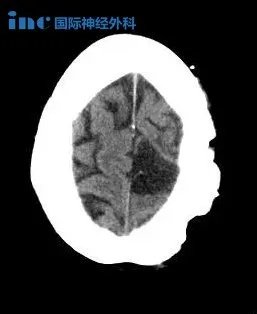

手术过程——左侧额叶到额顶叶旁矢状面的成骨性环锯术和显微外科脑膜瘤切除术;自体骨膜移植的硬脑膜成形术。手术成功,肿瘤全切、矢状窦成功重建、运动功能区无损伤。术后影像显示肿瘤肉眼下全切,可见局部组织缺陷,水肿效应存在,被压迫正常脑组织缓慢复位。

▼术后5年CT影像

术后第二天下午,王女士就能在医院护理人员的搀扶下进行走路康复训练。术后没有打抗生素,而且术后几天就可以独自走路,无需陪同。术后一周多已经恢复得和正常人一样,精神状态很好,可以在医院内自由散步,术后两周王女士顺利出院回国。